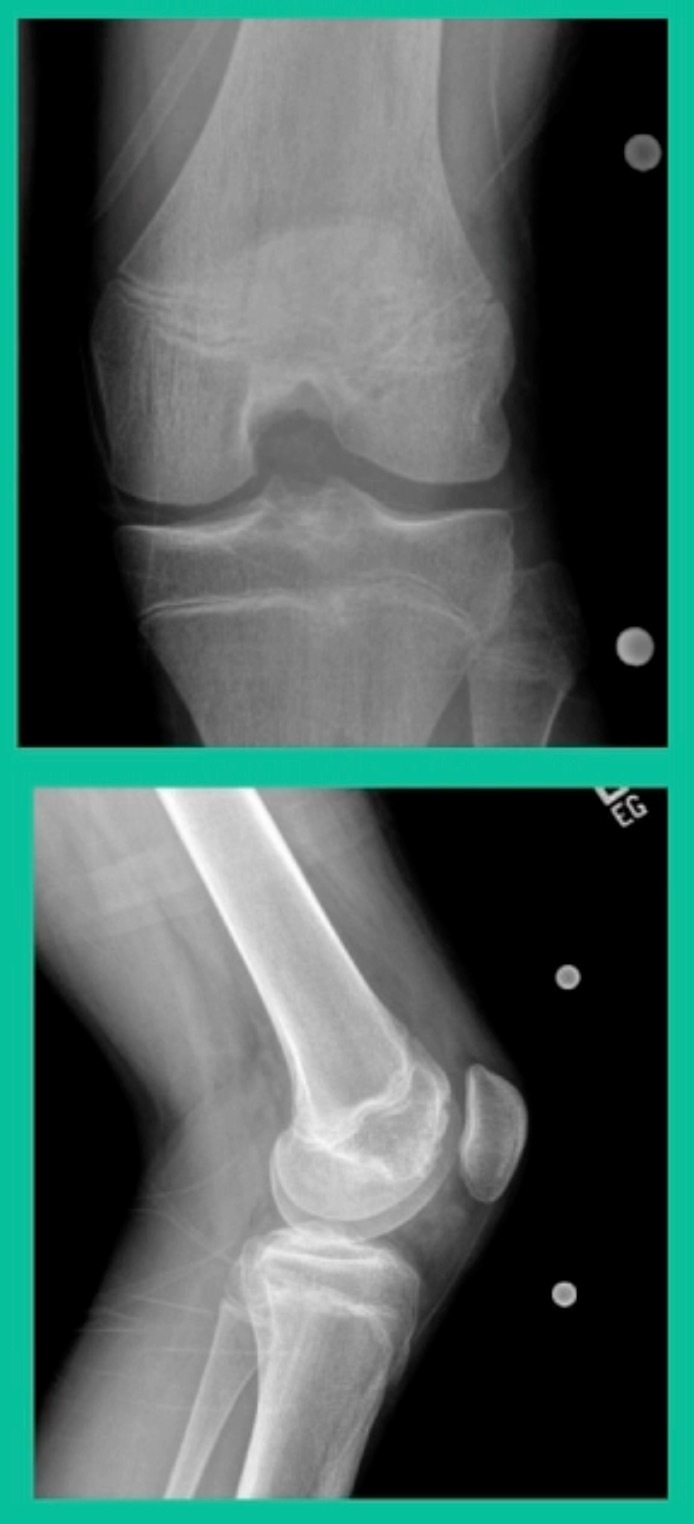

This is an 11-year-old. Left knee lateral knee pain. Effusions, the same type of classic findings (Figure 3)

You look at this one, you say, “what are you going to see when you get in there?” This is one when you get in there, you say, I’m not even sure I’m in the right knee because you almost don’t see it. That happens in patients who were painful, but they don’t look macroscopically unstable. Pediatric orthopedic surgeons tend to drill these. These are the ones that I see as failures. I think when you’re talking about something that’s mechanically unstable, it’s hard to understand why drilling would actually make it work without fixation. Even if it’s microscopically unstable.